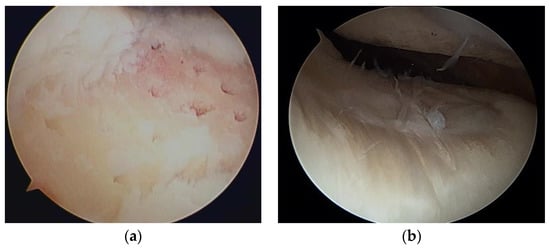

Steadman et al. [2] modified this method to avoid thermal necrosis from drilling, using bone marrow from the subchondral bone to form a clot on the defect holes (Figure 1). The clot contained mesenchymal stem cells (MSCs) and abundant growth factors, inducing repair by fibrous and hyaline-like cartilage [3] (Figure 2).

Figure 1. (a) Multiple holes drilled into a cartilage defect; (b) second-look arthroscopy 2 years later.